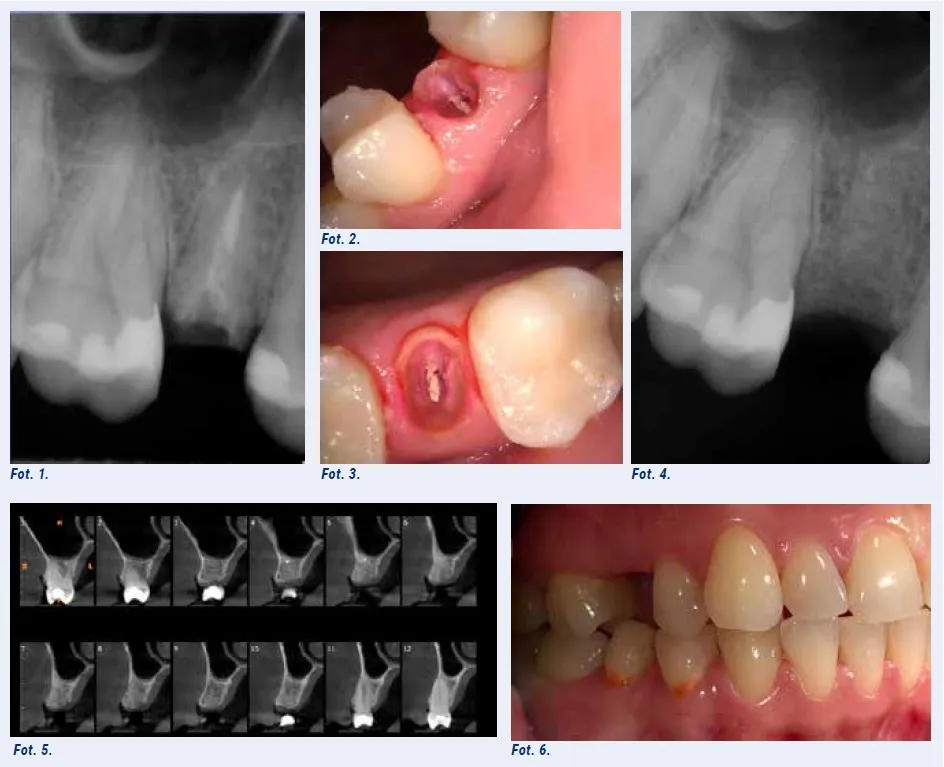

Natomiast chirurgiczne usunięcie zęba jest procedurą bardziej skomplikowaną. Jest konieczne, gdy ząb jest niewidoczny (np. zatrzymany w kości), złamany poniżej linii dziąseł, ma skomplikowany system korzeniowy (np. zakrzywione korzenie), lub jest otoczony przez torbiel. W takim przypadku chirurg stomatolog musi naciąć dziąsło, często usunąć fragment kości otaczającej ząb (tzw. dłutowanie), a następnie usunąć ząb, często w kilku fragmentach. Po usunięciu zęba rana jest oczyszczana i zszywana, co jest kluczowe dla prawidłowego gojenia. To właśnie te dodatkowe kroki sprawiają, że zabieg chirurgiczny jest bardziej zaawansowany i wymaga większej precyzji.

Pierwszym i najważniejszym krokiem jest zawsze dokładna konsultacja z chirurgiem stomatologiem. Podczas tej wizyty lekarz oceni stan zęba, zbierze wywiad medyczny i omówi plan leczenia. Niezbędna jest również odpowiednia diagnostyka obrazowa. Zazwyczaj wykonuje się pantomograficzne zdjęcie rentgenowskie (tzw. panorama), które daje ogólny obraz obu łuków zębowych. W przypadku bardziej skomplikowanych przypadków, zwłaszcza ósemek zatrzymanych lub zębów położonych blisko ważnych struktur anatomicznych (np. nerwu żuchwowego), konieczne może być wykonanie tomografii komputerowej (CBCT). To badanie dostarcza trójwymiarowego obrazu, co pozwala chirurgowi precyzyjnie zaplanować zabieg i zminimalizować ryzyko powikłań.

- Nacięcie dziąsła: Chirurg wykonuje niewielkie nacięcie w dziąśle, aby odsłonić ząb i otaczającą go kość. To pozwala na lepszy dostęp do obszaru zabiegowego.

- Usunięcie fragmentu kości (dłutowanie): Jeśli ząb jest zatrzymany w kości lub otoczony przez nią, konieczne może być delikatne usunięcie fragmentu kości za pomocą specjalistycznego wiertła. Odbywa się to z dużą ostrożnością, aby nie uszkodzić sąsiednich struktur.

- Usunięcie zęba: Za pomocą specjalistycznych narzędzi (dźwigni, kleszczy) ząb jest delikatnie uwalniany z zębodołu. W wielu przypadkach, zwłaszcza przy zębach o skomplikowanej budowie lub bardzo mocno osadzonych, ząb jest dzielony na mniejsze fragmenty, co ułatwia jego bezpieczne usunięcie.

- Oczyszczenie zębodołu: Po usunięciu zęba, zębodół jest dokładnie oczyszczany z wszelkich pozostałości (fragmentów zęba, kości, zainfekowanej tkanki). Czasami stosuje się płukanie solą fizjologiczną.

- Założenie szwów: Na koniec, dziąsło jest delikatnie zszywane. Szwy pomagają utrzymać tkanki w odpowiednim położeniu, co przyspiesza gojenie i zmniejsza ryzyko powikłań. Zazwyczaj stosuje się szwy rozpuszczalne, które same znikają po kilku dniach lub tygodniach, lub szwy nierozpuszczalne, które usuwa się po około 7-10 dniach.